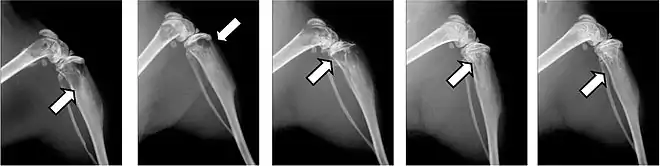

- Vues de fractures pathologiques

Fracture pathologique de l'humérus sur une métastase de carcinome du rein

Fracture pathologique du bras gauche sur une métastase osseuse de cancer du sein